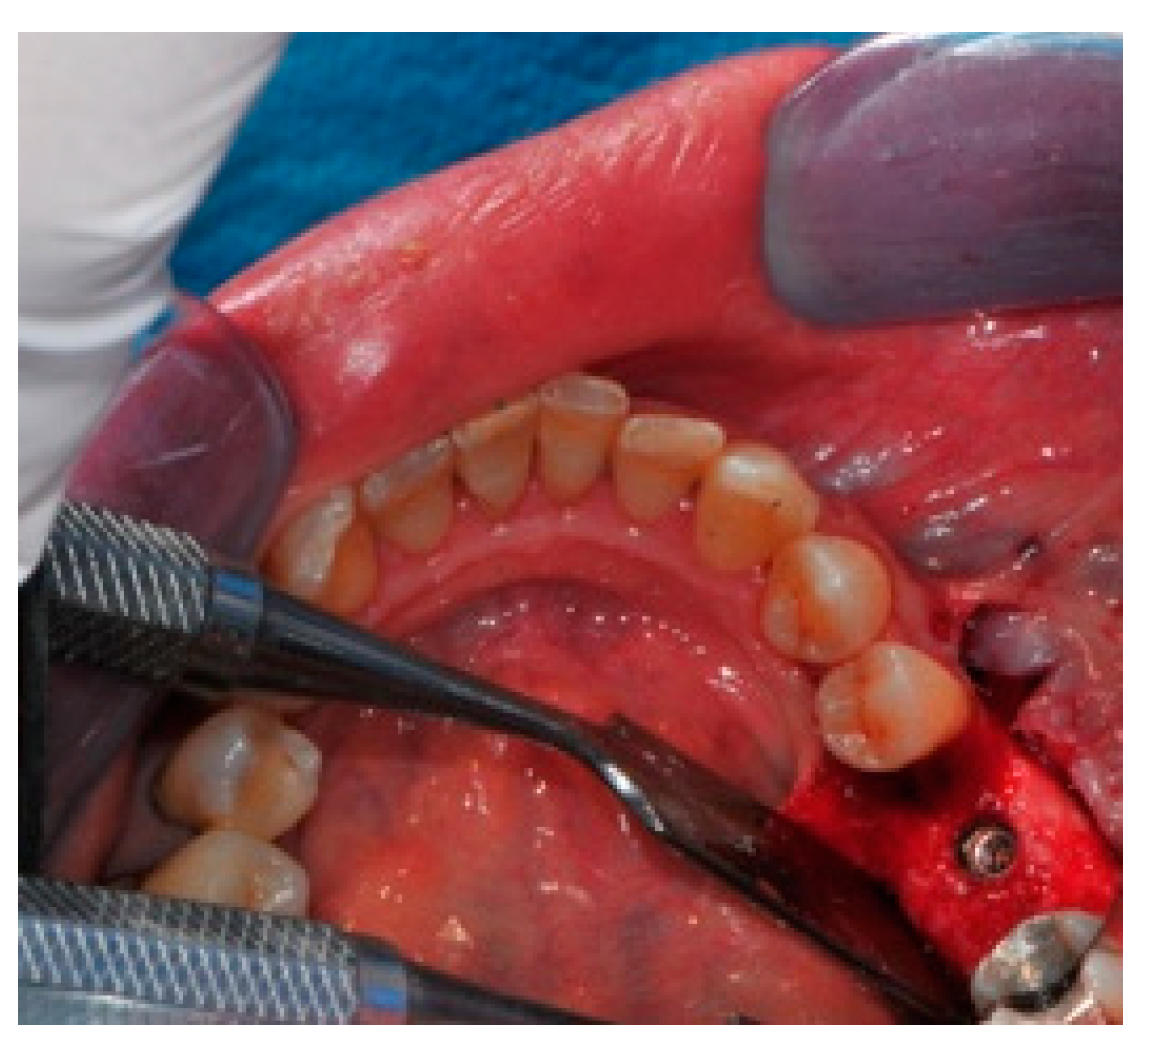

- Positioning of the customized titanium mesh: Being patient-customized or responding to the specific requirements of the patient in terms of planned bone augmentation, this mesh does not require any modification and it should perfectly fit the patient’s residual bone (Figure 8).

- Fixation and coverage: Fixation is a crucial aspect of the procedure as the stability of the graft must be maintained in order to ensure bone regeneration. The grid is fixed on the residual bone with titanium screws. Subsequently, the titanium mesh is covered with a resorbable membrane (Figure 9 and Figure 10).